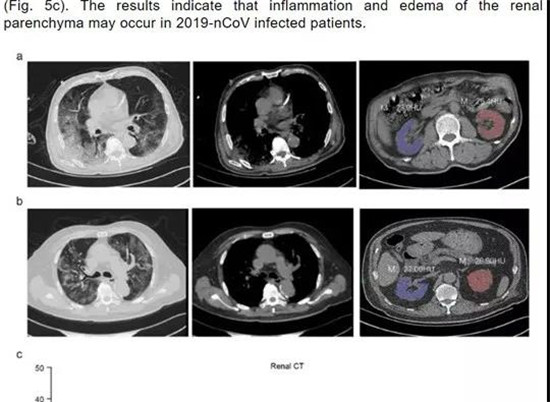

这份名为《Caution on Kidney Dysfunctions of 2019-nCoV Patients》的论文,研究了59名来源于武汉、黄石和重庆的59例感染患者病例。

结果发现, 63%的患者表现出肾功能不全的症状,CT扫描显示100%的患者肾脏影像学异常。